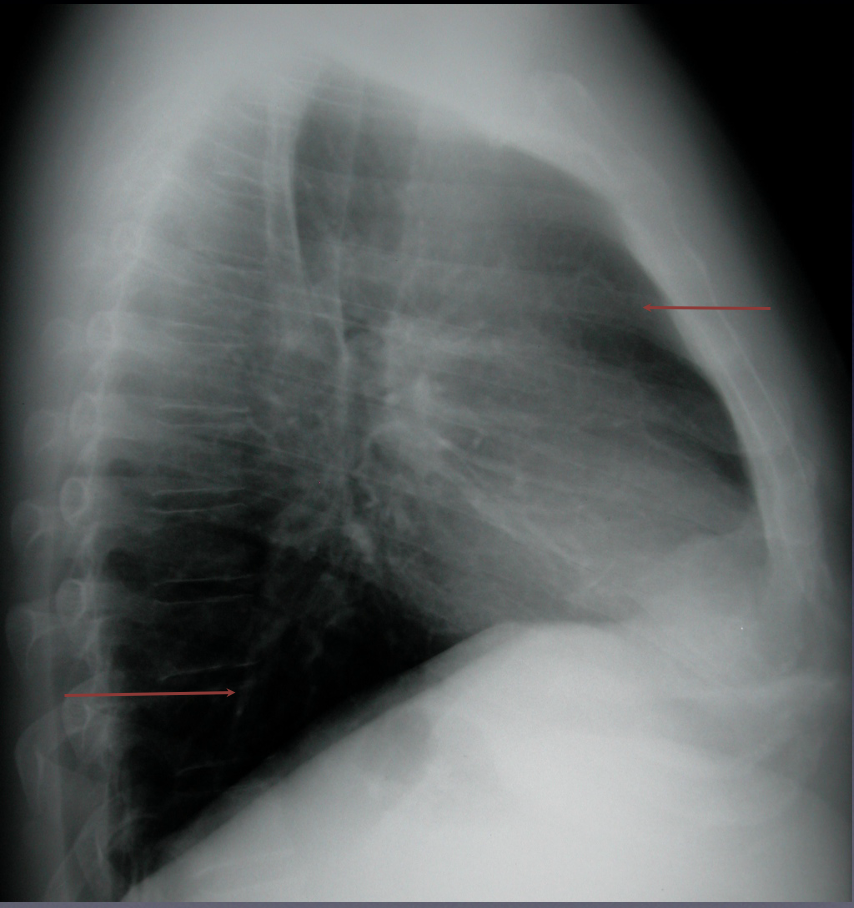

Go

The retrosternal and retrocardiac spaces should be dark on a lateral CXR.

-If they are not, disease is present

Normal CXR